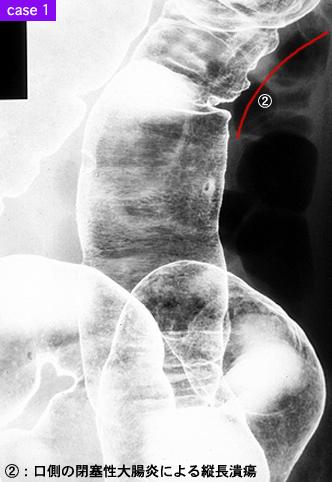

疾患(病理主体)の分類炎症性・潰瘍性疾患/その他

部位(臓器別)大腸/下行

検査方法X-P

病変の最大径(ミリ)40以上